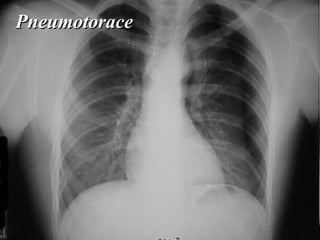

Pneumotorace